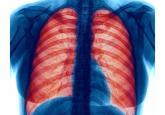

ArticleTreatment Options for Stable Chronic Obstructive Pulmonary Disease: Current Recommendations and Unmet NeedsAuthor:Victor Kim, MDPublish date: January 31, 2018Primary care physicians manage the care of approximately 80% of patients with COPD.Read More